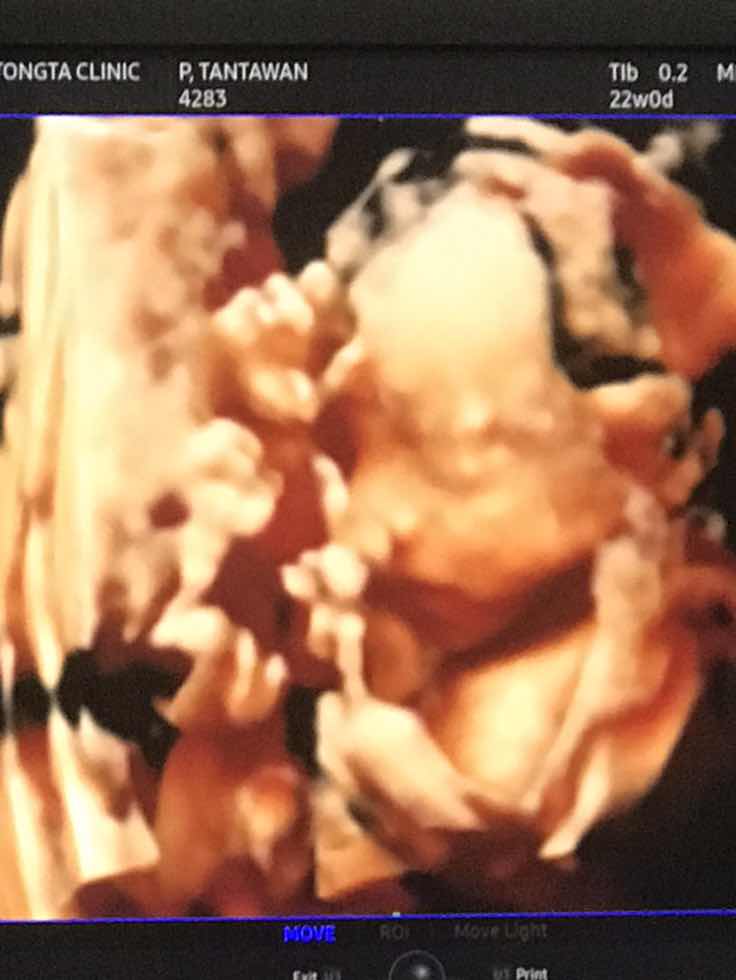

ขอดูรูปซาวของแม่ๆหน่อยค้าว่าได้ผู้หญิงผู้ชาย บ้านนี้ผู้ชายจ้าา

ลูกสาวค่ะ

ญ ค่ะ

ผญค่าา

ชัดมากคะ

จมูกกกก